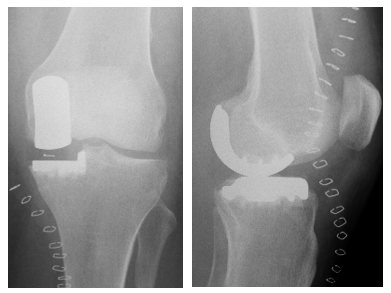

Abbildung 2:

Schematische und radiologische Darstellung der O-Bein- und X-Bein-Arthrose

(Fa. Aesculap und Bildmaterial der Orthopädischen Abteilung, Charité Berlin)